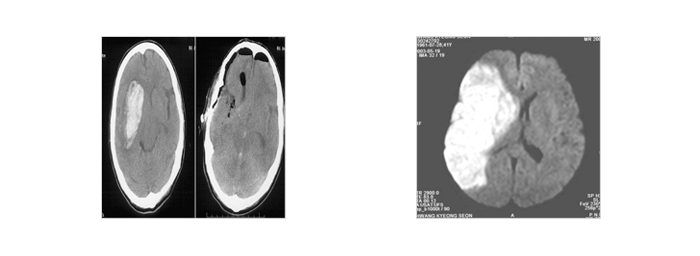

뇌졸중종류

뇌출혈(모야모야병,뇌동맥류,고혈압성 뇌출혈, 뇌동정맥기형 등)뇌경색(혈전성,색전성,열공성)

뇌출혈 - 사진, 일러스트